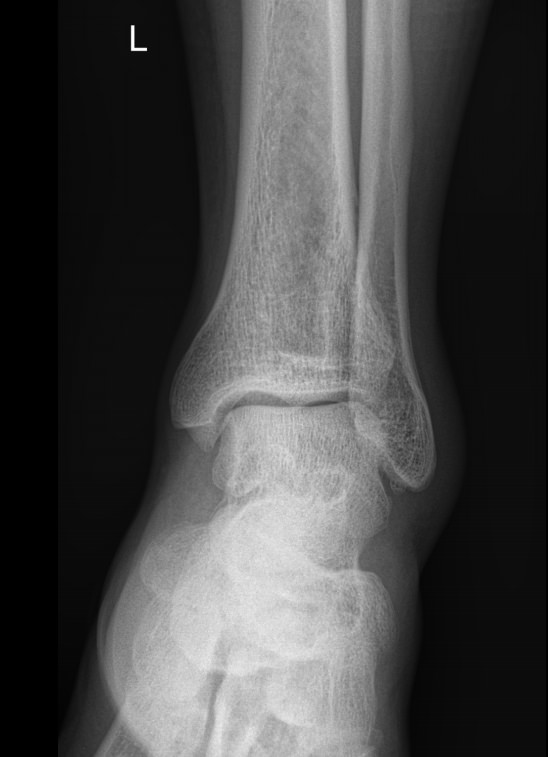

Сустав, соединяющий голень и стопу, наряду с коленным, выполняет важные функции перемещения тела в пространстве и поднятия собственного веса. Голеностоп имеет сложное строение и, как и любой другой сустав в теле человека, подвержен системным заболеваниям и травмам.

В диагностике патологий голеностопных суставов рентгеновское исследование относится к скрининговым, то есть первичным, методам. Действительно, рентген ― классический, простой, доступный и безболезненный способ получить информацию о внутреннем строении и патологических изменениях, произошедших в суставе. А благодаря современным цифровым аппаратам исследование становится и практически безопасным, так как несет минимальную дозу облучения.

Что покажет рентген голеностопного сустава

В описании врач указывает патологические изменения, если они есть в следующих образованиях:

• Суставные щели;

• Соответствие друг другу суставных поверхностей;

• Костная ткань и надкостница;

• Мягкие ткани.

Также подробно описываются переломы, вывихи, новообразования, их местоположение и особенности.